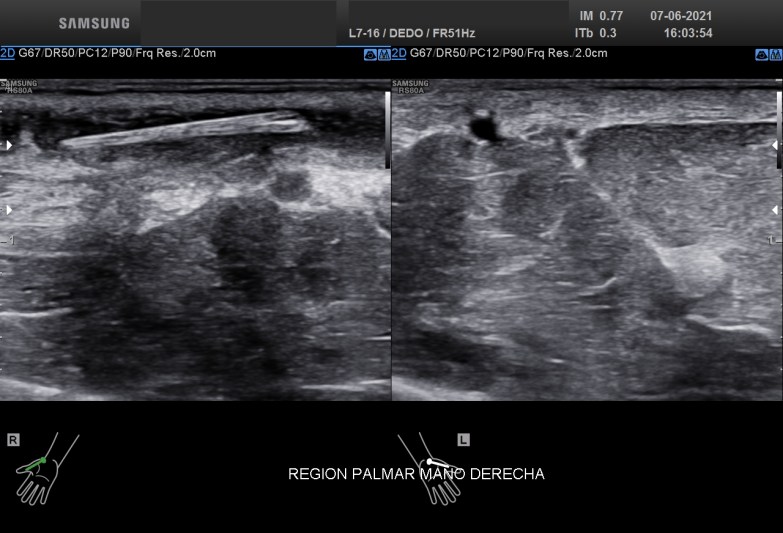

Con una sonda de ultra alta frecuencia realizo la exploración de dicha región objetivando estas imágenes que te muestro:

En el corte axial o eje corto que realicé sobre la zona afecta encontrémoslas rápidamente una estructura redondeada, hiperecogénica, al rededor de ella una pequeña cantidad de líquido y un engrosamiento importante del tejido circundante de lo que era claramente un cuerpo extraño.

El corte longitudinal o en eje largo la ecoestructura alargada, hiperecogénica se hace claramente con el protagonismo de la imagen, el líquido en este eje parece mayor, y la zona de afectación de esta estructura alojada en el TCS es mucho mayor de lo que parecía en un principio.

En este momento nos hace falta claramente la anatomía, saber perfectamente donde está alojada la ecoestructura o cuerpo extraño que está provocando claramente una reacción a cuerpo extraño. Se demuestra que la situación es subcutánea, no afecta a vasos y no afecta al tejido muscular. En el Tejido Celular Subcutáneo existe claramente cambios en la ecoarquitectura normal de la región, con presencia de líquido y aumento global de las partes blandas del tejido graso. El líquido parece estar floculado, es espeso y además no es anecoico, con lo que podríamos estar delante de algún tipo de infección local que se confirmó tras la extirpación del cuerpo extraño y que precisó tratamiento antibiótico y que queda demostrado en la imagen 3 y la imagen 4.